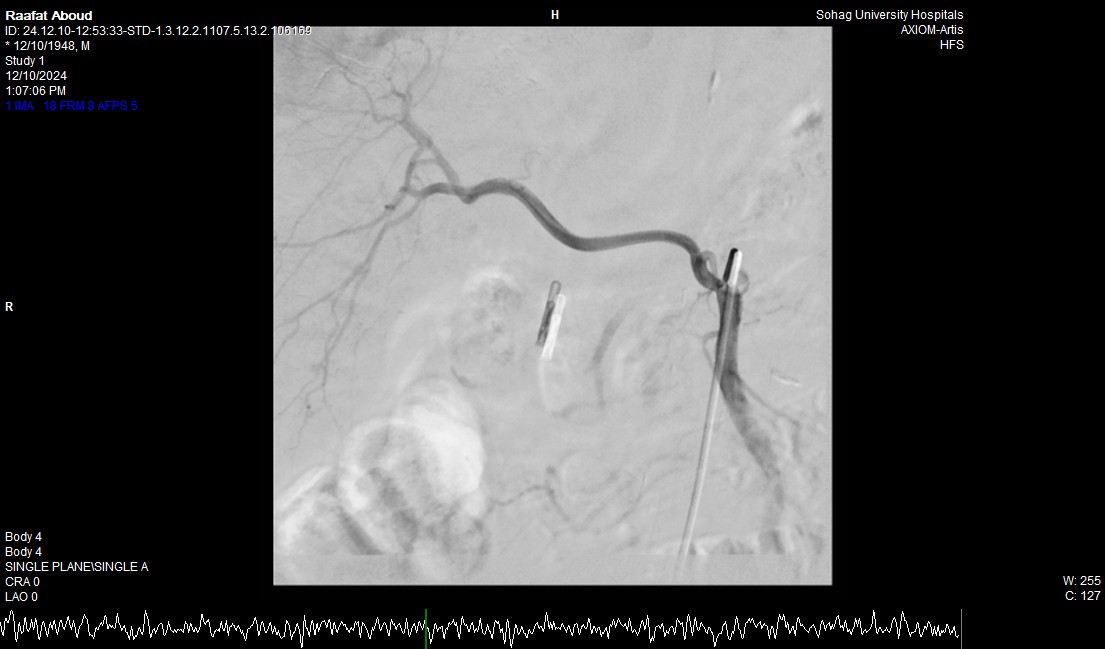

جامعة سوهاج.. أفاد الدكتور أحمد كمال، المدير التنفيذي للمستشفيات الجامعية، أن الفحوصات أظهرت وجود قرحة كبيرة في الاثني عشر وشريان نازف. نجح الفريق الطبي في التحكم بالنزيف مبدئيًا عبر تركيب مشبك معدني بالمنظار وحقن القرحة النازفة.

جامعة سوهاج.. وفي خطوة لاحقة، تم استدعاء فريق الأشعة التداخلية الذي تمكن من إغلاق الشريان النازف بشكل عاجل باستخدام جهاز القسطرة، ما ساهم في استقرار حالة المريض.